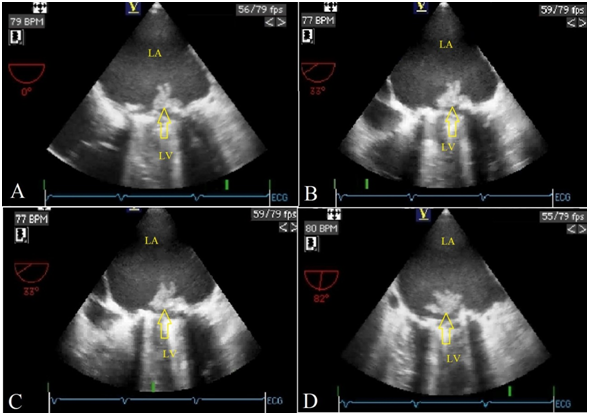

A 48-year old man was consulted to cardiology for 39°C fever and ongoing dyspnea for 2 days during his hospitalization in the intensive care unit. He had undergone mechanical mitral valve replacement 3 years earlier. His history included a dental procedure without antibiotic prophylaxis 15 days ago. The chest radiogram was unremarkable. Transthorasic echocardiography revealed a mass on the mechanical mitral prosthesis and increased transvalvuler gradients with decreased valve area (Figure 1) Subsequently, transesophageal echocardiography (TEE) was performed which showed  a large obstructive mass on the prosthetic valve, protruding  into the left ventricular cavity during diastole. It was observed that, the cross sectional images of the mass was resembling various animal shapes in different multiplane TEE views. A rabbit like image was obtained from midesophageal transverse plane (0 degrees) (Figure 2A) (Video 1). Whereas on 33 degrees, the same image resembled to a mouse head (Figure 2B) (Video 2). Interestingly, after clockwise rotation of the probe shaft at the same degree the mouse image turned into a cow’s head with its horns (Figure 2C). Finally, with the transducer array at 82 degrees, the vegetation looked like a flapping pigeon (Figure 2D) (Video 3). Consequently the patient underwent redo valve surgery and was discharged after an uneventful postoperative period. Since two-dimensional TEE provides cross sectional analysis of cardiac strutures, masses with irregular borders can be viewed as different shaped images in different TEE views.1 We considered this case valuable as 4 different animal-like images were depicted  in the same patient.

Figure 2 Two-dimensional transesophageal echocardiography showing a rabbit like image , obtained from midesophageal transverse plane (0 degrees). (A) An image resembling to a mouse head with big ears, eyes and long nose at 33 degrees. (B) Clockwise rotation at 33 degrees resulted in a cow’s head image with its horns. (C) With the transducer array at 82 degrees, a pigeon image was obtained with it’s wings, tail and opened beak. (D) (LA, Left atrium; LV, Left ventricle).